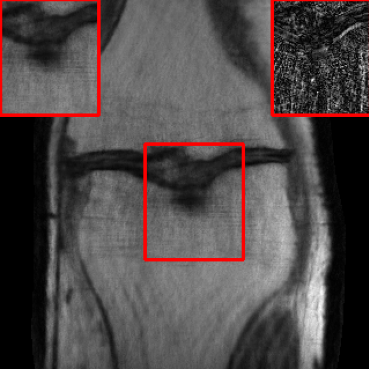

| Ground Truth | LORAKI | Global | LONDN-MRI | LONDN-MRI | Oracle |

![]() |

| PSNR = dB | PSNR = 33.21 dB | PSNR = 36.12 dB | PSNR = 36.31 dB | PSNR = 36.54 dB | PSNR = 36.71 |